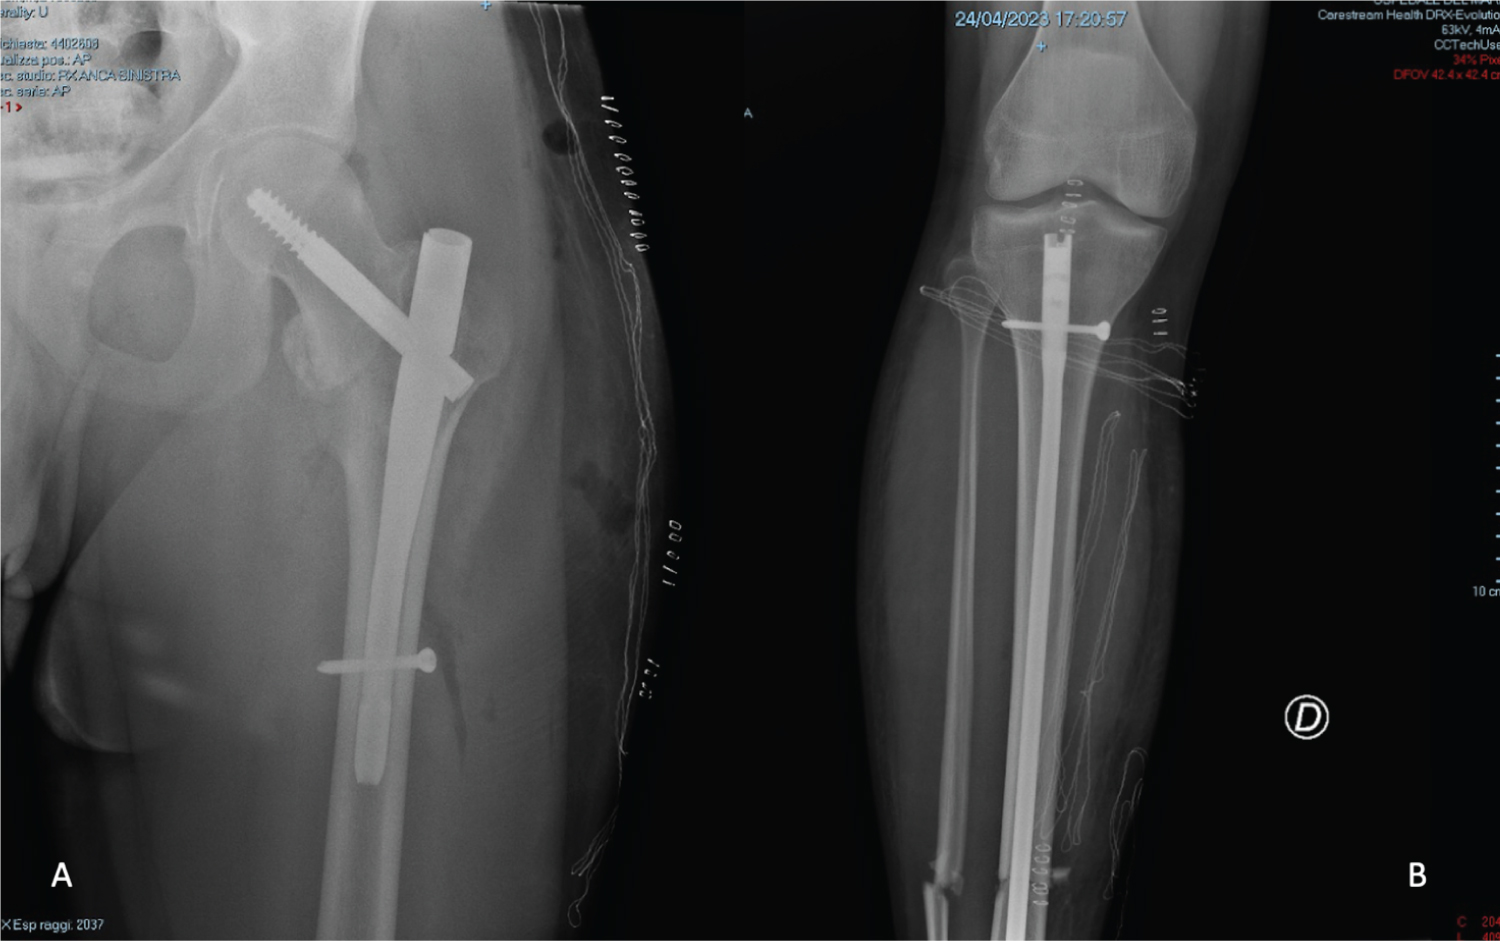

A 20-years-old male was admitted to our emergency department for a road car accident with a diagnosis of bilateral lower extremities fractures (tibial shaft fracture and femoral neck fracture. After six hours he underwent a surgical intervention of endomedullary nailing for both fractures (Figure 1). Before surgery, this patient was conscious at all times but 24 hours after surgery, he manifested state of confusion, with episodes characterized by delusional ideation, confabulation and psychomotor agitation. On neurological physical examination, the patient was alert, disoriented in time, cranial nerves appeared uninjured, and there were no focal limb signs. Brain CT scan and electroencephalogram showed no abnormalities. Due to the persistence of the symptomatology, MRI of the brain was performed, which showed multiple, millimeter-long areolae of pathological signal restriction in DWI study sequences at the bilateral nucleocapsular region, corona radiata, deep white matter and juxtacortical on both sides as well as at the posterior frontal cortical site. Additional similar areas were found at the posterior median and paramedian right commissural region and at bilateral retro trigonal site. These findings were compatible with multiple embolic-based ischemic foci in an evolving phase (Figure 2). There is no specific treatment for fat embolism or fat embolism syndrome. Therapy included prophylaxis stroke with aspirin at a daily dose of 100 mg, Low Molecular Weight Heparin (LMWH) 4000 IU once day and Dexamethasone 4 mg intravenous twice daily. After one day, the patient appeared markedly improved, alert, conscious and cooperative, oriented in time, with fluent speech, normal pupillary reflex, preserved strength, sensitivity and coordination, absent meningeal symptoms. The patient during hospitalization practiced echocardiographic "bubble-test" with evidence of suspected atrial septal defects (ASDs) at the level of the caval septum with left-to-right shunt and passage of microbubbles of moderate entity. Transesophageal echocardiography could not be performed because of the patient's difficulty in lying lateral decubitus. After 10 days, the patient repeated brain MRI that showed attenuation of known ischemic lesions (Figure 3).

Figure 1: Post-operative X-Ray. View Figure 1